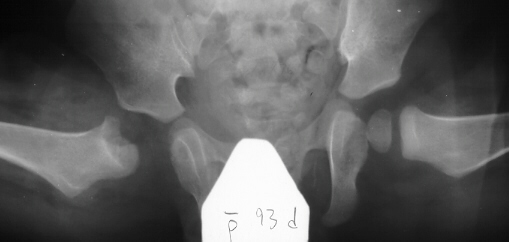

- Post Operative Day 18: R hip Xray: subluxation of R hip, possible metaphyseal

lucency consistent with osteomyelitis. Taken to OR for repeat I & D

of R hip via posterior approach with Penrose drains and hip spica cast

(15cc seropurulent fluid drained). Antibiotics changed to Oxacillin 225mg

IV q4.

Institute. Initial labs: WBC 15,100, ESR 72. R hip Xray: changes in proximal

. metaphysis including lucency and demineralization, hip subluxated. Treated

with oxacillin and Pavlik harness.